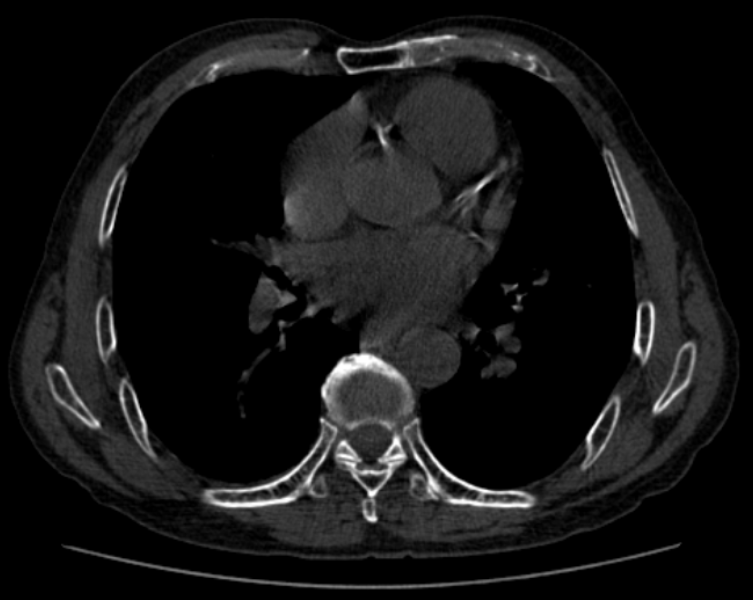

这是一项无创、无需注射造影剂的平扫检查。它就像给血管做了一次“灰度扫描”,数一数上面有多少钙化点。

注射少量碘造影剂后,通过CT扫描,计算机能把心脏血管的走行、分支、狭窄处重建出一张高清的3D立体图像。